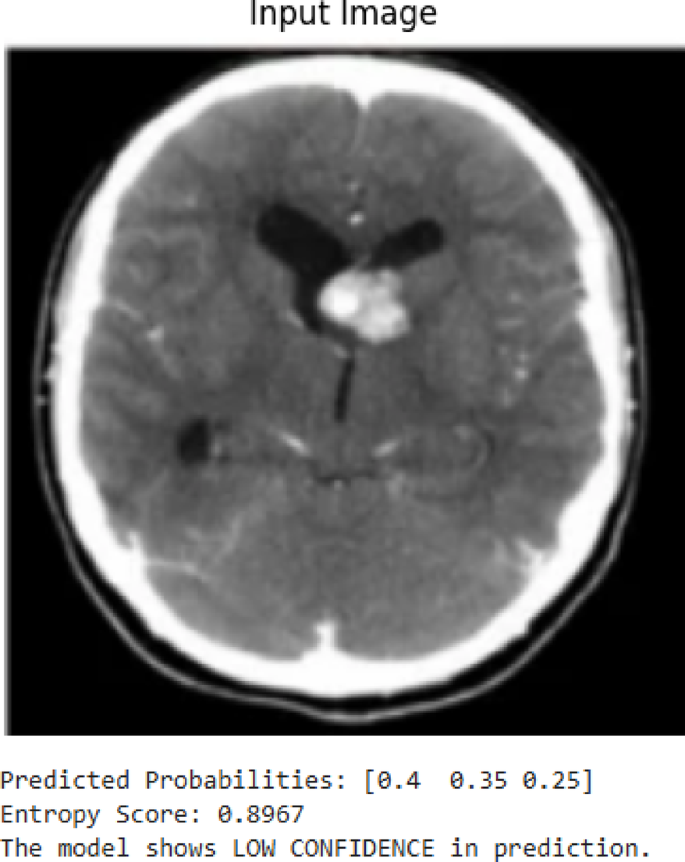

Entropy-based uncertainty estimation

For each model prediction, this study computed entropy as a measure of prediction uncertainty. Although the entropy values were not used to modify training or inference outcomes, study analyzed them post hoc to assess their potential as clinical triage signals. Specifically, study examined predictions exceeding an empirically determined entropy threshold (based on validation set distribution) as candidate low-confidence cases, envisioned for secondary review in a clinical workflow.

The technique outlined in this work, called Guided Grad-CAM, merges the benefits of guided backpropagation and Grad-CAM to give a full image of the locations leading to the model’s prediction. The overlay in Fig. 21 shows the specific locations in the brain MRI image that the model is concentrating on, particularly the area surrounding the tumor. The areas receiving the greatest focal point from the model are represented by patches of green and blue, and the overlay demonstrates how these areas impact the decision class. This method provides a more complete and accurate explanation for why a model is seeing what it sees to ensure that the model’s focal point is clinically aligned. In this study, LIME is used to identify the decision boundaries of the ensemble model as further evidence of the ways these different features drive one classification decision to the next. In Fig. 22, using LIME, this study provides an interpretable explanation for the model’s prediction of class 2. The red and green markings highlight which parts of the MRI image contributed most to the classification decision. Certain red sections are damaging to the prediction, while the green sections pose a positive increase to the prediction. As a byproduct of perturbing the original image and then testing how those perturbed images change the model’s decision, LIME enables, even approximates identification of the decision boundary by providing explanations of why this model predicted that class. This kind of openness gives physicians the ability to evaluate whether the model’s prediction is consistent or reasonable with medical expertise.

LIMA XAI heatmap.